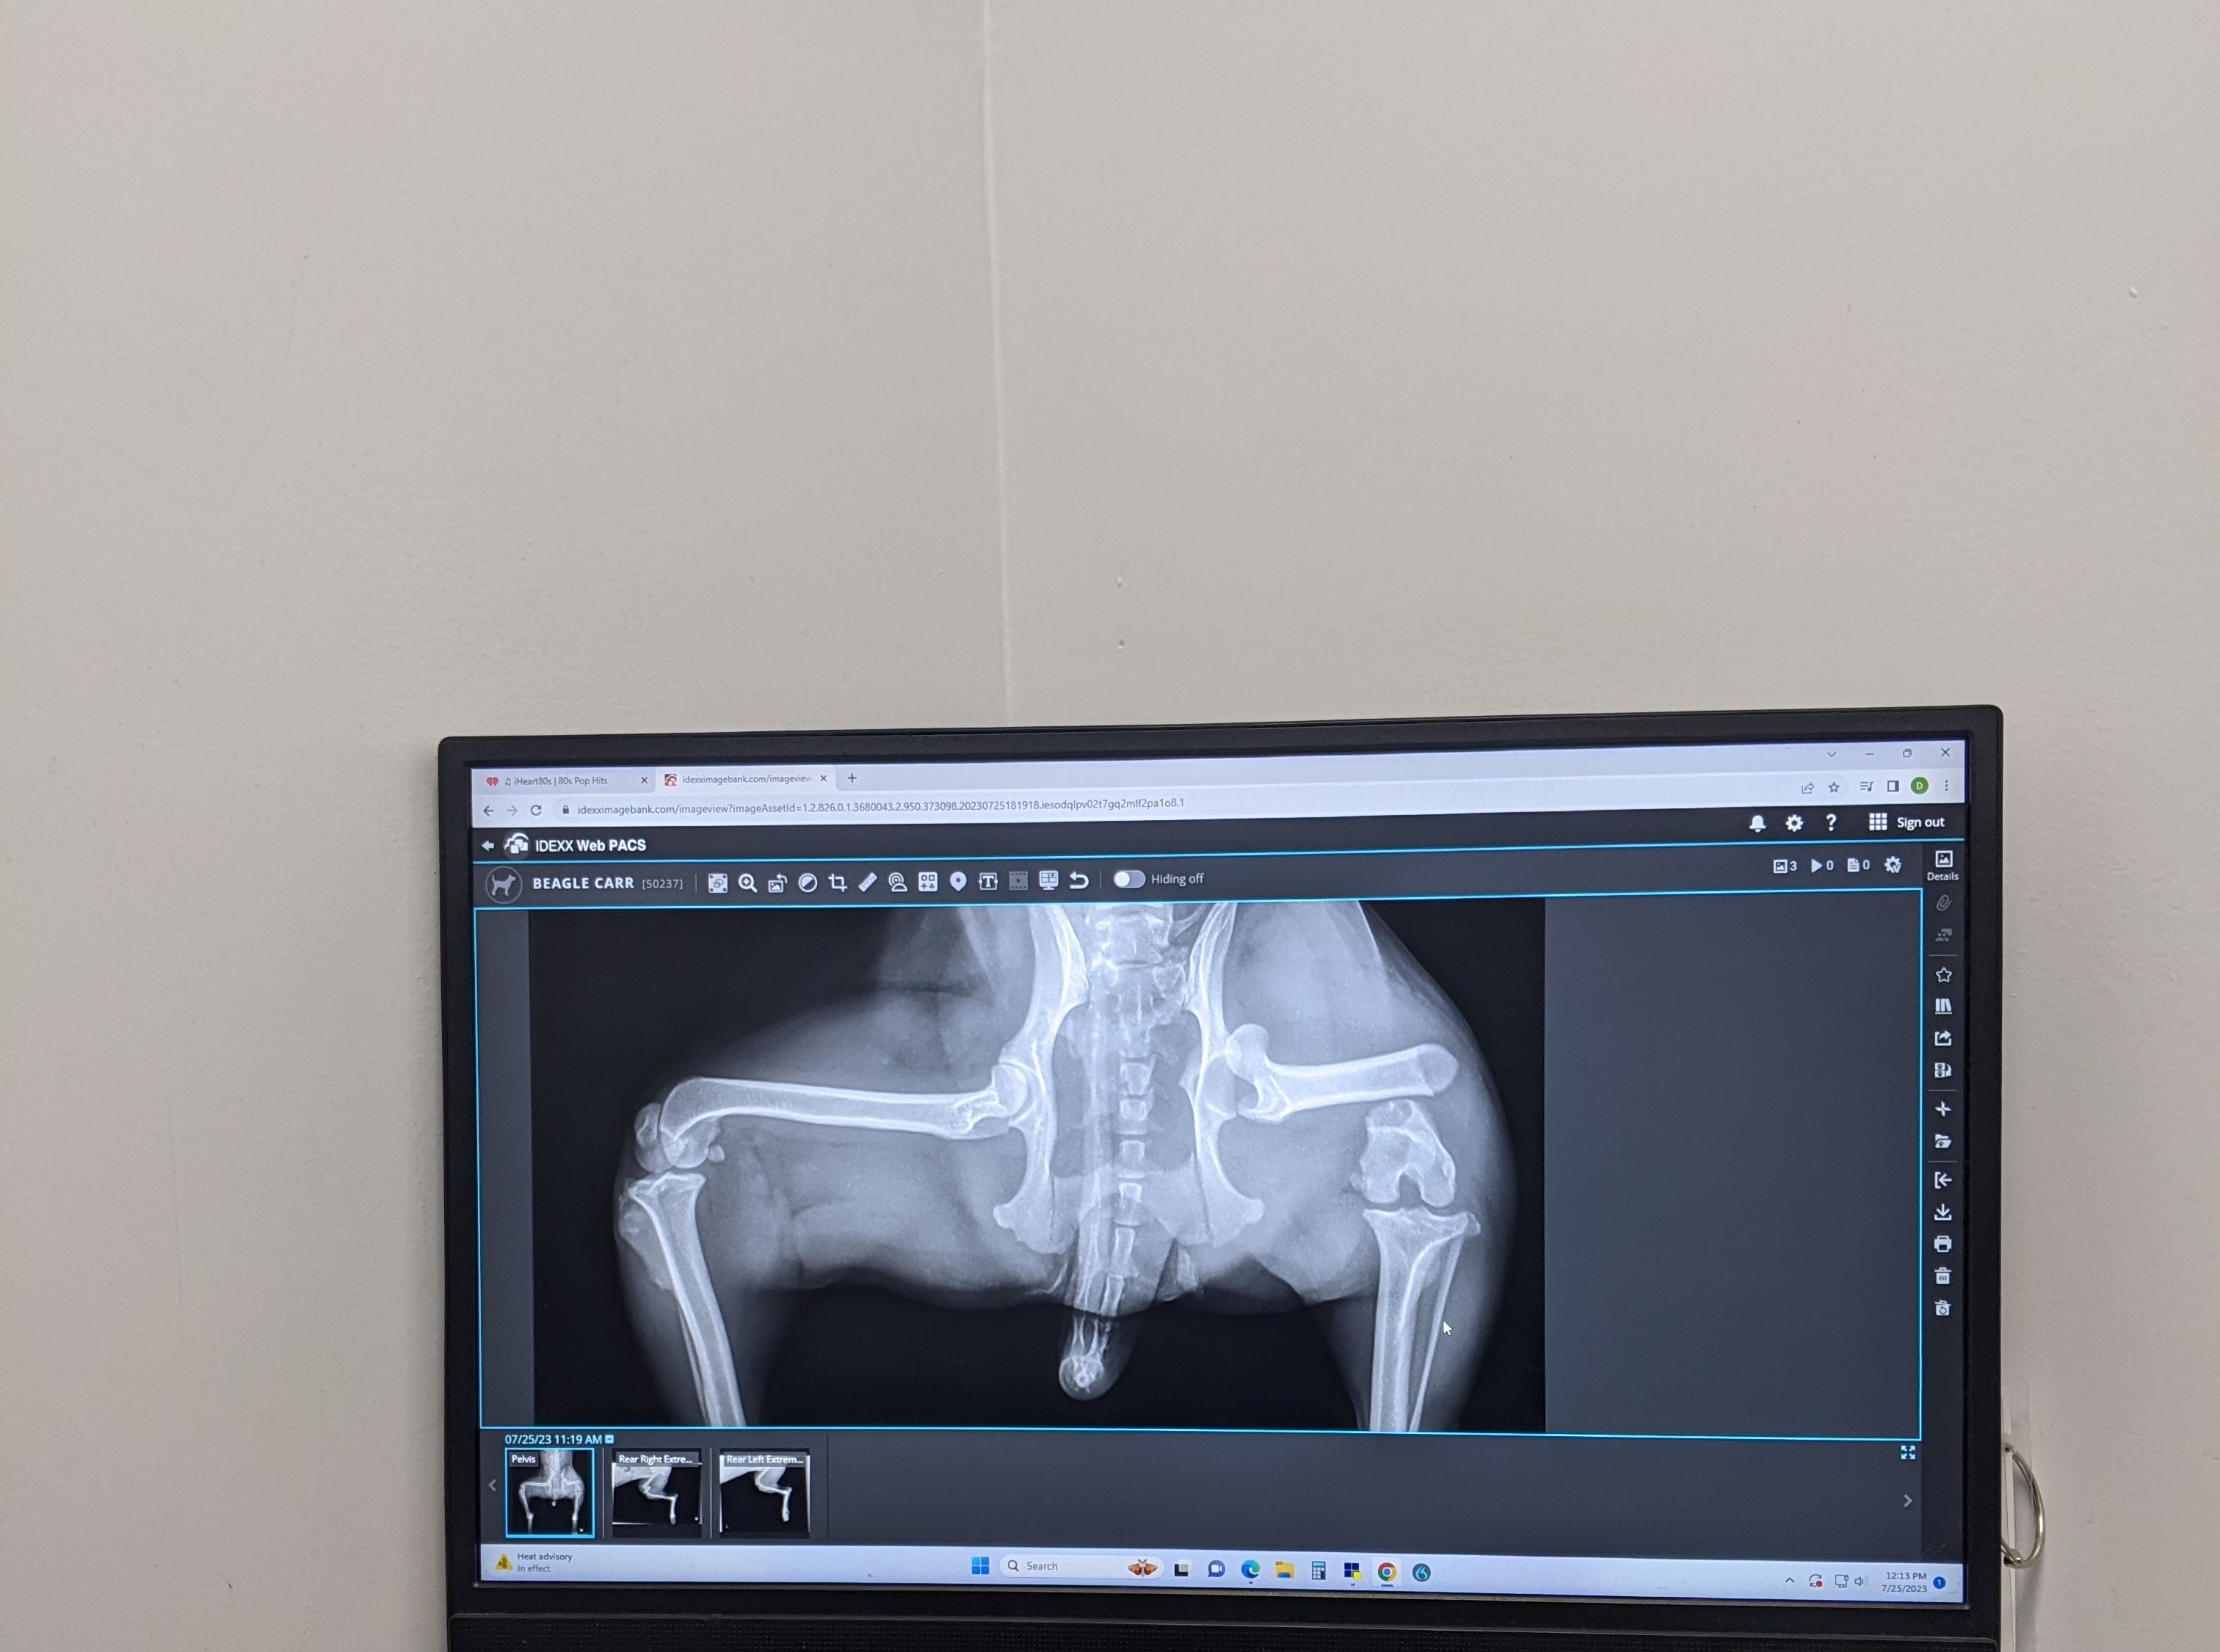

Sadly, Cruiser and two other stray dogs were hit by a car while living on the street. The other two dogs had already passed when a good samaritan stopped to help, but they were able to get Cruiser to a nearby veterinarian. There, vets found that he sustained several major injuries, including a broken hip, fractured right rear leg, and urethrorectal/perianal fistula (abnormal passageways developing between the urethra and the rectum). While the kind person who brought him in couldn’t afford the treatment for his veterinary care, they did contact Beagles and Buddies in Apple Valley, California, to help.

Someone from the nonprofit was able to pay for his surgery ($7000 including their discount for being a rescue), stay with him overnight, and then transfer him to the rescue to recover. They were given two options when it came to his shattered hip and broken leg–to amputate or to do reconstructive surgery. They opted for femoral head ostectomy surgery and placed a metal plate on his leg. With enough downtime during recovery before physical therapy, they believed Cruiser would retain mobility in his leg. And they were right!